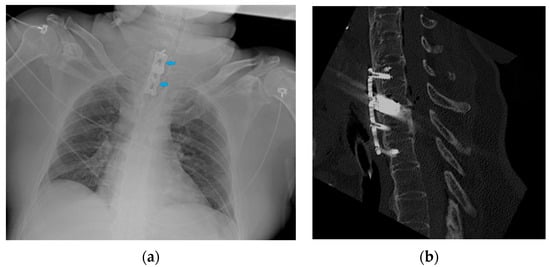

7. Chest Tubes

8.1. Cerebrospinal Fluid (CSF) Shunts

8.3. Other Devices